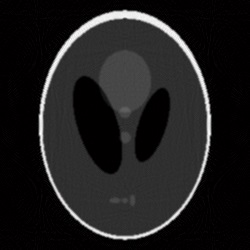

We have presented in [3] a method of calculating (by direct approximation) the right-hand side of (2), and showed that it obtains more accurate reconstruction as compared to the filtered back-projection algorithm (for the case of sparse view scanning with at most 180 projection angles). The result obtained through this direct integration method, for the example with 270 projection angles, is shown in Fig. 3.

Given the problems we have pointed out regarding the first randomized algorithm, we have focused on the results obtained by the second randomized algorithm. For the parameters that we have fixed above, the results obtained by running the second randomized algorithm with 125000 iterations are given in Fig. 4 and Fig. 5 (Fig. 4 (a) is Fig. 2, and Fig. 5 (a) is Fig. 3). In both cases, the correction is significant, and the result of correction is very close in terms of reconstruction quality to the result obtained by running each of the two analytical algorithms alone with full view of 360 projection angles. That is, the result shown in Fig. 4 (b) is comparable to the result shown in Fig. 6, and the result shown in Fig. 5 (b) is comparable to the result shown in Fig. 7, which means a reduction in the number of views of (in Figs. 6 and 7 the reconstruction is more homogeneous, but with more visible artifacts). From the experiments we have conducted, we have remarked that the number of views can be reduced up to about and the results are still comparable to the results obtained by the analytical algorithms with full view, provided an appropriate number of iterations is chosen.